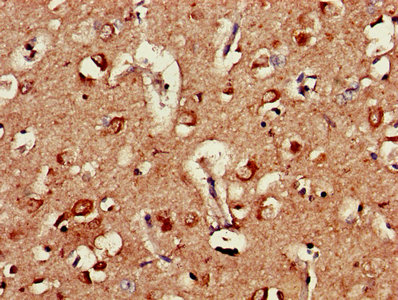

Immunohistochemistry of paraffin-embedded human brain tissue using CSB-PA00625A0Rb at dilution of 1:100